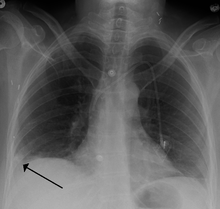

A Hampton hump in a person with a right lower lobe pulmonary embolism

Segmental and subsegmental pulmonary emboli on both sides